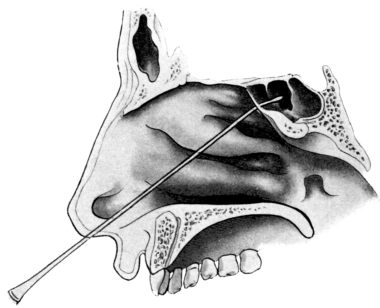

| 210. | Passing the Eustachian Catheter | 365 |

| 211. | Passing the Eustachian Catheter | 365 |

| 212. | Passing the Eustachian Catheter | 366 |

| 213. | Passing the Eustachian Catheter | 366 |